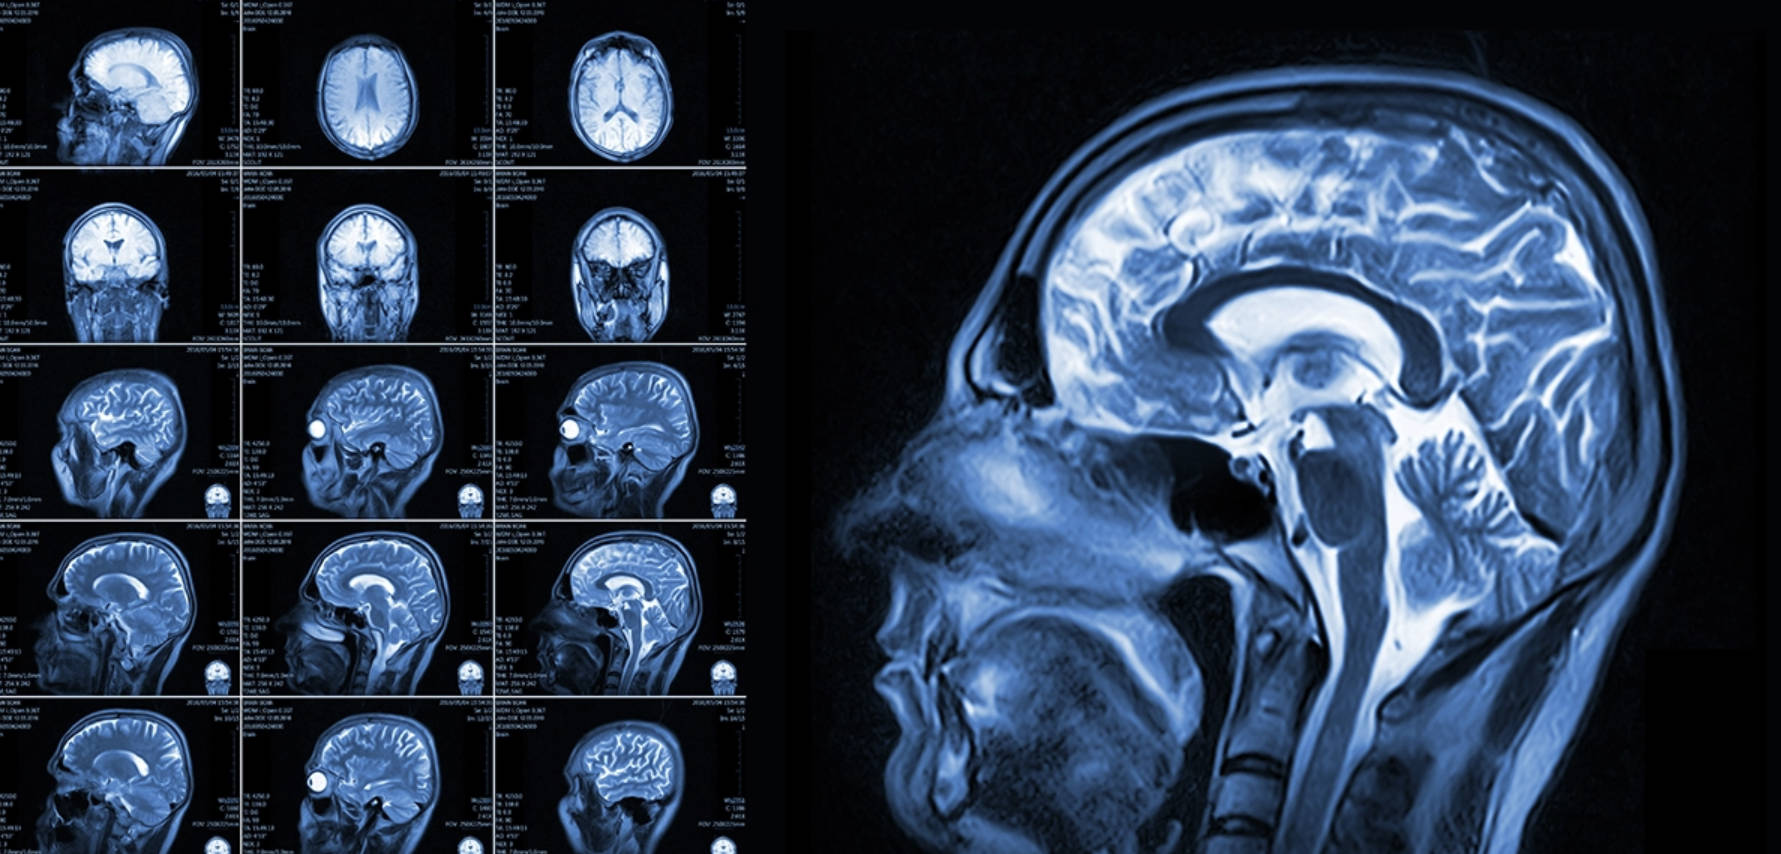

3. ماگنىتلىق رېزونانس (MRI) – يۇمشاق توقۇلمىلارنىڭ «رادارى»

MRI پۈتۈنلەي باشقىچە تېخنىكا بولۇپ، ئۇنىڭدا X نۇرى ئىشلىتىلمەيدۇ.

MRI نىڭ ئاساسىي نەزەرىيەسى بولغان يادرو ماگنىتلىق رېزونانس ھادىسىسى 1940-يىللاردا بايقالغان بولسىمۇ، ئۇنى تەسۋىر ھاسىل قىلىشقا ئىشلىتىش ئىدىيىسى 1973-يىلى ئامېرىكىلىق خىمىيە ئالىمى پول لائۇتېربۇر (Paul Lauterbur) تەرىپىدىن ئوتتۇرىغا قويۇلغان. كېيىنچە ئەنگىلىيەلىك پېتېر مەنسفىلىد (Peter Mansfield) بۇ تېخنىكىنى تېخىمۇ مۇكەممەللەشتۈرۈپ، تەسۋىر ئېلىش سۈرئىتىنى تېزلىتىش ئۇسۇلىنى تاپقان ۋە تۇنجى ئادەم بەدىنىنى سىكانىرلاش 1977-يىللىرى مۇۋەپپەقىيەتلىك ئېلىپ بېرىلغان. رادىئاتسىيەسىز تەكشۈرۈش ئېلىپ بارالايدىغان بۇ تېخنىكا ئۈچۈن لائۇتېربۇر ۋە مەنسفىلىد 2003-يىلى نوبېل مۇكاپاتى بىلەن تەقدىرلەنگەن.

- ئىشلەش پرىنسىپى: كۈچلۈك ماگنىت مەيدانى ۋە رادىئو دولقۇنى ئىشلىتىلىدۇ. بەدىنىمىزدىكى سۇ تەركىبىدىكى ھىدروگېن ئاتوملىرىنىڭ ماگنىتقا بولغان ئىنكاسى ئارقىلىق تەسۋىر ھاسىل قىلىنىدۇ. شۇڭا سۇ تەركىبى كۆپ بولغان يۇمشاق ئەزالارنى ئىنتايىن ئېنىق كۆرسىتىدۇ.

- ئەڭ ماس كېلىدىغان ئورۇنلار:

- يۇمشاق توقۇلمىلار: مېڭە، يىلىك، نېرۋا سىستېمىسى، مۇسكۇل، پەي ۋە بوغۇم كېسەللىكلىرى.

- مېڭە تىقىلمىسى (يېڭى قوزغالغان): مېڭىگە قان چۈشۈش ياكى قان يېتىشمەسلىكنى ئەڭ بالدۇر بايقايدۇ.

- بەل ئومۇرتقا ئارىلىق تەخسىسى تومپىيىپ چىقىش: بەل ئاغرىقىنىڭ سەۋەبىنى ئېنىقلاشتا ئەڭ ياخشى قورال.

- ئۆسمە: ئۆسمىنىڭ ئورنى ۋە خاراكتېرىنى ئېنىقلاشتا مۇھىم.

- ئارتۇقچىلىقى: رادىئاتسىيە يوق (بەدەنگە زىيانلىق نۇر چىقارمايدۇ). يۇمشاق توقۇلمىلارنى CT دىنمۇ ئېنىق كۆرسىتىدۇ.

ماگنىتلىق رېزونانس (MRI) نىڭ كەمچىلىكى:

- مېتال چەكلىمىسى: ئەڭ چوڭ كەمچىلىكى بەدەندە مېتال بارلار (مەسىلەن: يۈرەك رىتىمىنى تەڭشىگۈچ، كونا تىپتىكى مېتال چىش، سۆڭەك مىخلىرى) چۈشۈشكە بولمايدۇ، چۈنكى كۈچلۈك ماگنىت بۇ مېتاللارنى تارتىپ كېتىشى ياكى قىزىتىۋېتىشى مۇمكىن.

- ۋاقىت ئۇزۇن ۋە بوشلۇق تار: ئوخشىمىغان تەكشۈرۈشلەر جەريانى 2 مىنۇتتىن بىر سائەتكىچە سوزۇلىدۇ. ماشىنىنىڭ ئىچى تار بولغاچقا، يېپىق بوشلۇقتىن قورقىدىغانلار (Claustrophobia) غا تەس كېلىدۇ.

- شاۋقۇن ۋە ھەرىكەت: تەكشۈرۈش جەريانىدا «تاراق-تۇرۇق» قىلغان ئاۋاز بەك چوڭ چىقىدۇ. بىمار ئازراقلا مىدىرلاپ قويسا، پۈتۈن سۈرەت قالايمىقانلىشىپ كېتىدۇ، كىچىك بالىلار، بوۋاقلارنى تارتىش بىر قەدەر تەس بولىدۇ، شۇڭلاشقا ئۇلارنى ناركوزلاش ئارقىلىق ئۇخلىتىپ تارتىلىدۇ.